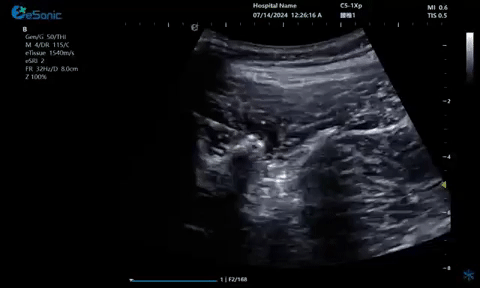

超声引导硬膜外麻醉-小等号

管内麻醉